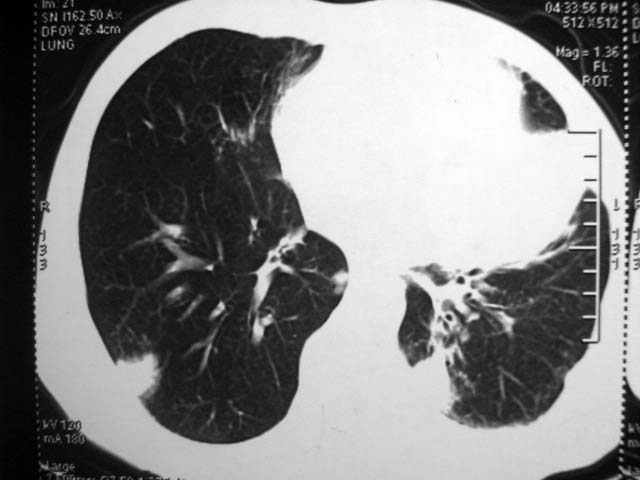

标题: CT17875:肺曲霉菌病?结核? [打印本页]

标题: CT17875:肺曲霉菌病?结核?

男,52岁,发热2月,糖尿病史。

抗结核治疗irpz方案,血糖未治疗,空腹15.9左右。症状无好转,左胸痛。

复查ct

2、双肺见多发片状及结节状高密度影,大多数病灶中心均见“空泡征”。

结果:两肺继发性肺结核并曲霉菌感染。